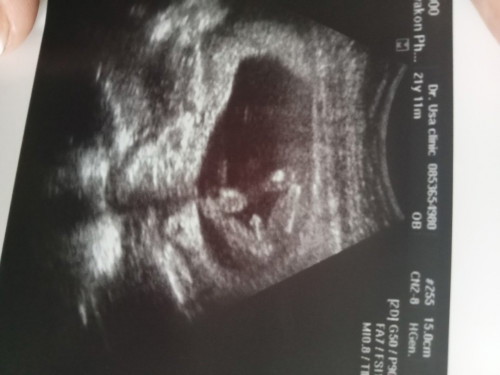

แม่ๆบ้านอื่นกี่วีคกันแล้วคะทราบเพศกันรึยังคะบ้านนี้16W3Dแล้วค่ะเห็นชัดมาก🤣🥰👶

บ้านนี้ตอนแรกไปซาวด์15วีคหมอเห็นแวบเดียวค่ะว่าผู้ชายแต่น้องหนีบไวมากหมอเลย ไม่คอนเฟิร์มแต่รอบนี้ชัดเลยค่ะ อาจจะเห็นนะคะแม่ขึ้นอยู่ท่าที่น้องอยู่ด้วยค่ะว่าจะให้เห็นมั้ย